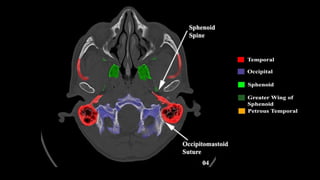

Pseudo-fractures

Extrinsic Fissures &

Sutures